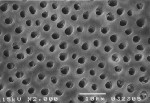

Figure 2 provides SEM views of the surface of untreated dentin (Figure 2a) and a well-mineralized area of the dentin due to treatment with the professional desensitizer (Figure 2b). The surface was covered with a thick layer of highly coherent mineral, blocking the tubules. It may be noted that not all of the dentin treated with the professional desensitizer was well mineralized. Presumably, it was this lack of complete coverage that resulted in the dentin permeability not having been further reduced.